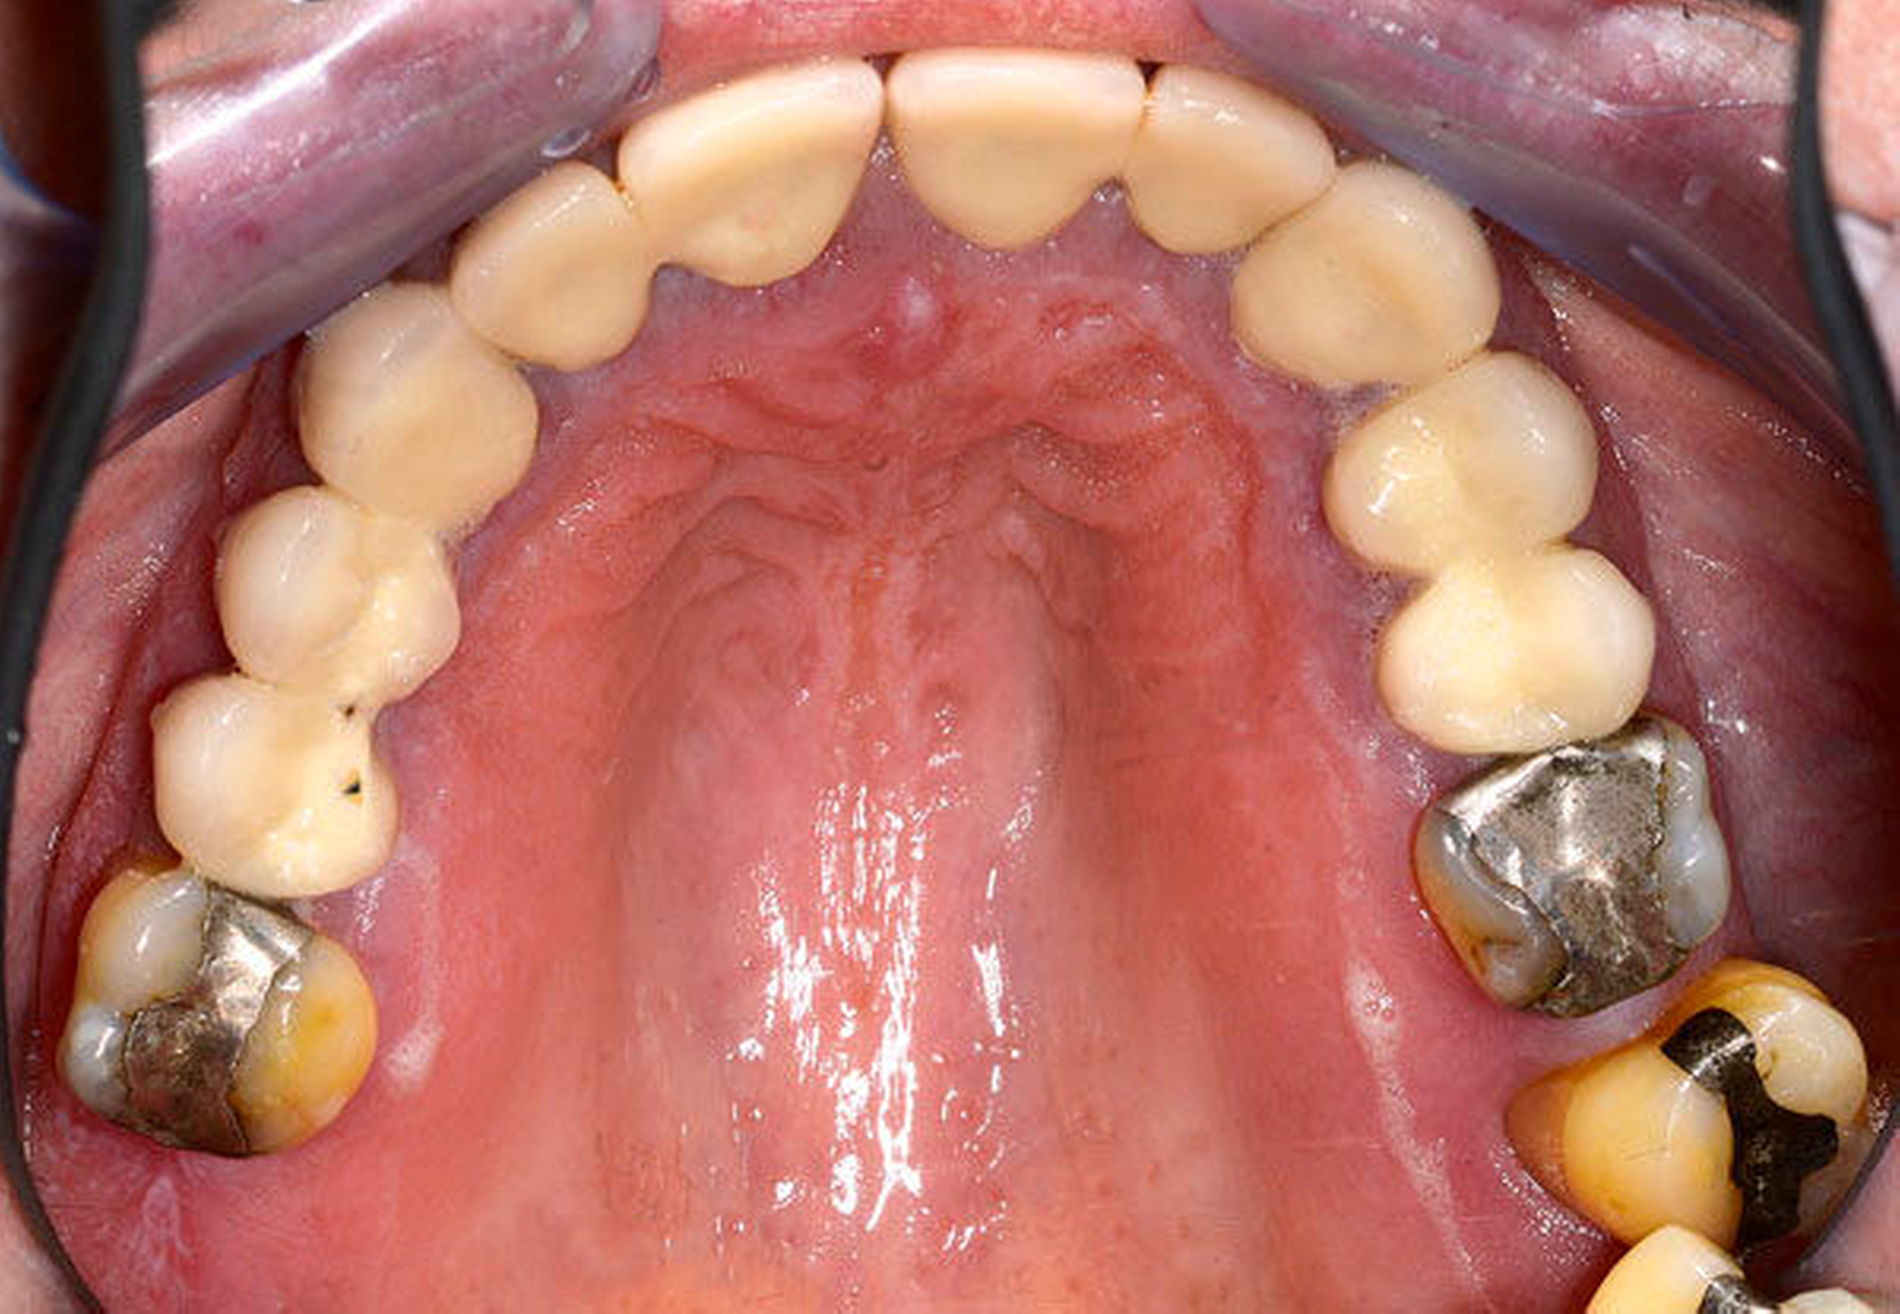

Der Plaqueindex PCR betrug 72 Prozent [O`Leary TJ et al., 1972] und der gingivale Blutungsindex GBI 75 Prozent [Ainamo J et al., 1975]. Das alio loco angefertigte Orthopantomogramm (Abbildung 3) zeigte horizontalen Knochenabbau bis zu einem Drittel der Wurzellänge in beiden Kiefern. Die Zähne 16 und 26 wiesen einen Knochenabbau > 2/3 der Wurzellänge auf. Am Zahn 27 mesial erreichte der Knochenabbau die Wurzelspitze; zudem war der Zahn elongiert und wies eine Kippung nach distal auf. In einer ersten Einzelzahnprognose wurden alle Zähne mit Ausnahme von Zahn 27 als sicher eingestuft. Prothetisch war die Patientin im OK mit einer Brücke (13 bis 15), Kronenblöcken (21/11, 21/22, 24/25) und Amalgamfüllungen an den Zähnen 16 und 26 sowie im UK mit einer geschiebeverankerten Modellgussprothese versorgt.

Neben der Medikamentensubstitution gilt die Plaque- und Entzündungskontrolle als vorrangig therapeutisch beeinflussbar [Lederman D et al., 1984; Seymour RA et al., 2000, Seymour RA, 2006; Thomas DW et al., 2000]. Hierzu zählen Plaque- und Zahnsteinentfernung sowie die Korrektur von Plaqueretentionsstellen. Diese Maßnahmen wurden im dargestellten Fall intensiv durchgeführt. Durch die multiplen Überkronungen lagen zahlreiche subgingival gestaltete und überkonturierte Kronenränder sowie Kronenverblockungen als begünstigende Plaqueretentionsstellen vor. Diese waren jedoch nicht mit einem vertretbaren Aufwand korrigierbar. Adjunktiv zur mechanischen Therapie wurde Chlorhexidingel zur chemischen Belagskontrolle eingesetzt. Auf die kontrovers diskutierte Gabe von Antibiotika wurde verzichtet [Thomas DW et al., 2006].